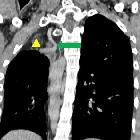

Right sided

lobar agenesis with multiple uncommon vascular anomalies – a rare case. Coronal image shows Abundant extrapleural fat seen in right upper hemithorax (yellow triangle), prominent right superior intercostal vein (green arrow).